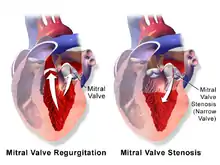

Mitral regurgitation (MR), also known as mitral insufficiency or mitral incompetence, is a form of valvular heart disease in which the mitral valve is insufficient and does not close properly when the heart pumps out blood.[3][4][5] It is the abnormal leaking of blood backwards – regurgitation from the left ventricle, through the mitral valve, into the left atrium, when the left ventricle contracts.[4] Mitral regurgitation is the most common form of valvular heart disease.[3]

Mitral regurgitation, also known as mitral insufficiency or mitral incompetence, is the backward flow of blood from the left ventricle, through the mitral valve, and into the left atrium, when the left ventricle contracts, resulting in a systolic murmur radiating to the left armpit.[5][3]

The mitral valve apparatus comprises two valve leaflets, the mitral annulus, which forms a ring around the valve leaflets, and the papillary muscles, which tether the valve leaflets to the left ventricle and prevent them from prolapsing into the left atrium. The chordae tendineae is also present and connects the valve leaflets to the papillary muscles. Dysfunction of any of these portions of the mitral valve apparatus can cause regurgitation.

The most common cause of MR in developed countries is mitral valve prolapse.[10] It is the most common cause of primary mitral regurgitation in the United States, causing about 50% of cases. Myxomatous degeneration of the mitral valve is more common in women as well as with advancing age, which causes a stretching of the leaflets of the valve and the chordae tendineae. Such elongation prevents the valve leaflets from fully coming together when the valve closes, causing the valve leaflets to prolapse into the left atrium, thereby causing MR.

Rheumatic fever (RF), Marfan's syndrome and the Ehlers–Danlos syndromes are other typical causes.[6] Mitral valve stenosis (MVS) can sometimes be a cause of mitral regurgitation (MR) in the sense that a stenotic valve (calcified and with restricted range of movement) allows backflow (regurgitation) if it is too stiff and misshapen to close completely. Most MVS is caused by RF, so one can say that MVS is sometimes the proximal cause of MI/MR (that is, stenotic MI/MR) and that RF is often the distal cause of MVS, MI/MR, or both. MR and mitral valve prolapse are also common in Ehlers–Danlos syndromes.[11]